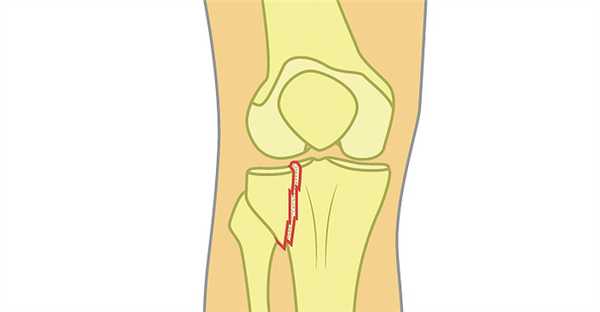

Перелом мыщелков большеберцовой кости

Перелом мыщелков большеберцовой кости - это нарушение целостности боковых отделов верхней части большеберцовой кости. Относится к числу внутрисуставных переломов. Может сопровождаться смещением или вдавлением отломков. Проявляется резкой болью, гемартрозом, выраженным ограничением движений в коленном суставе и нарушением опоры. Диагноз уточняют при помощи рентгенографии, реже используют КТ. Тактика лечения зависит от вида перелома, может использоваться гипсовая повязка, скелетное вытяжение и различные хирургические методики.

Перелом мыщелков большеберцовой кости - внутрисуставное повреждение боковых отделов верхнего эпифиза большеберцовой кости. Обычно сопровождается смещением или вдавлением участка суставной поверхности, поэтому характеризуется склонностью к развитию посттравматического артроза. Составляет примерно 13% от общего количества повреждений трубчатых костей, выявляется у людей любого возраста и пола, нередко встречается в составе политравмы. Переломы мыщелков могут сочетаться с повреждением связок коленного сустава, повреждениями менисков, переломами малоберцовой кости и межмыщелкового возвышения.

Возможные переломы со смещением и без смещения. Чаще всего диагностируются переломы наружного мыщелка большеберцовой кости, второе место по распространенности занимают переломы обоих мыщелков и третье - поражения внутреннего мыщелка. Открытые переломы составляют около 8% от общего числа травм. Согласно классификации AO (универсальной международной классификации переломов длинных трубчатых костей) различают три типа поражений мыщелков:

Симптомы перелома мыщелков

В момент травмы появляется резкая боль в колене. Колено увеличено в объеме, при переломе внутреннего мыщелка большеберцовой кости может выявляться варусная деформация, при переломе наружного - вальгусная. Опора существенно ограничена, активные движения отсутствуют, пассивные резко ограничены из-за боли. Самостоятельный подъем выпрямленной конечности невозможен. Наблюдается патологическая подвижность при боковых движениях в суставе.

При осмотре выявляется увеличение поперечника большеберцовой кости на уровне мыщелков по сравнению со здоровой стороной. Аккуратно надавливая на мыщелки одним пальцем, обычно можно четко определить зону максимальной болезненности. Имеется выраженный гемартроз, который иногда становится причиной нарушений местного кровообращения. Объем сустава увеличен, переднебоковые зоны над и под надколенником выбухают из-за скопления жидкости.